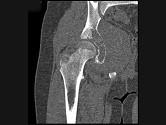

问题 男,15岁,右髋部疼痛、红肿,有压痛,皮温增高,结合图像,最可能的诊断是?(?)

选项 A.骨肉瘤 B.急性骨髓炎 C.尤文肉瘤 D.转移性神经母细胞瘤 E.骨结核

答案 C